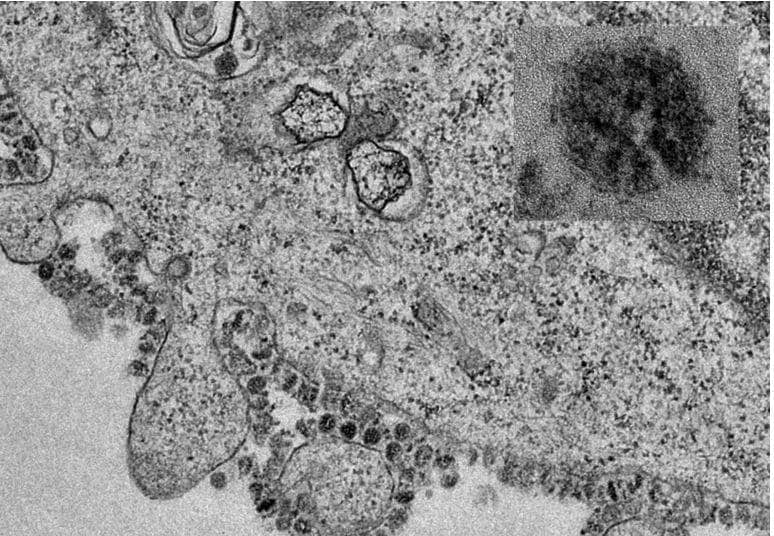

कोरोना वायरस की असली तस्वीर देखी! माइक्रोमीटर का है 1000वां हिस्सा

कोरोना वायरस ने चीन में कहर मचा रखा है और अब तक इस खतरनाक वायरस ने वहां तीन सौ से ज्यादा लोगों की जान ले ली है जबकि कई लोगों की हालत गंभीर है. पूरी दुनिया इस वायरस से डरी हुई है और वैज्ञानिक दिन-रात इसके वैक्सीन की खोज में डूबे हुए हैं. अब माइक्रोस्कोप के जरिए बेहद खतरनाक कोरोना वायरस की असली तस्वीर भी दुनिया के सामने आ गई है जो लोगों को चौंका रही है.

माइक्रोस्कोप के जरिए कोरोना वायरस की जो तस्वीर सामने आई है, उसमें यह वायरस एक मिलीमीटर के एक लाखवें हिस्से के छोटे टुकड़े में विभाजित करना होगा, ताकि इसे मापा जा सके.

शोधकर्ताओं ने हाल ही में कोरोना वायरस (2019-nCoV) से चीन में सैकड़ों मौत होने के बाद इस जानलेवा वायरस को लेकर माइक्रोस्कोप से ली गई तस्वीरें जारी की हैं. इस वायरस ने पूरे महाद्वीप को अपनी चपेट में ले लिया है और कई अंतर्राष्ट्रीय संस्थाओं ने इसे सार्वजनिक स्वास्थ्य के लिए आपातकाल घोषित किया है.

हांगकांग यूनिवर्सिटी के एलकेएस फैकल्ट ऑफ मेडिसिन ने इस जानलेवा और खतरनाक वायरस के तस्वीर की कॉपी जारी की है. इस वायरस का आकार माइक्रोमीटर में है जो एक मिलीमीटर का हजारवां हिस्सा है. वायरस 20 नैनोमीटर के बीच व्यास में होते हैं. एक नैनोमीटर एक माइक्रोमीटर का एक हजारवां हिस्सा है.